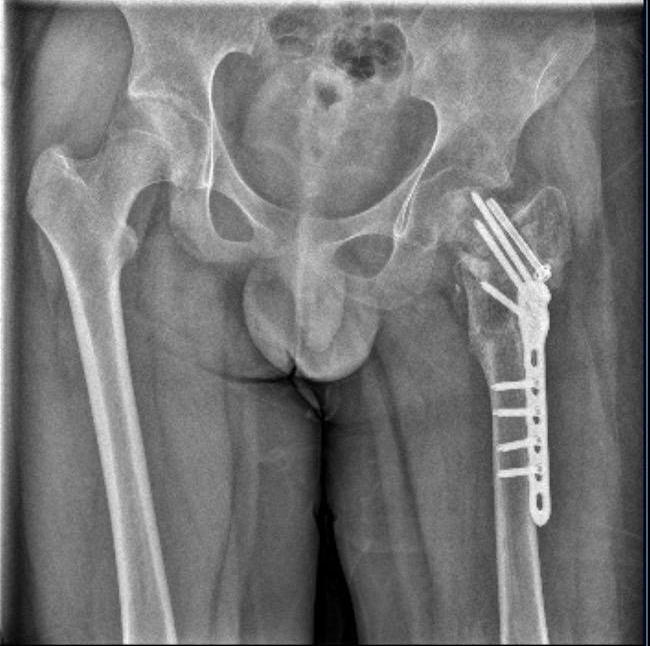

小武左股骨陈旧性骨折,打了钢针、钢板 图据受访人

7月,晋江市公安局对小武被故意伤害一案立案侦查。随后,晋江市公安局对小武进行了人体损伤程度鉴定,8月29日出具的《鉴定意见通知书》显示,小武三个部位不同程度损伤,其中,“左髋部重伤二级,胸部轻伤一级,双下肢轻微伤”,同时,其左股骨打了钢针、钢板。